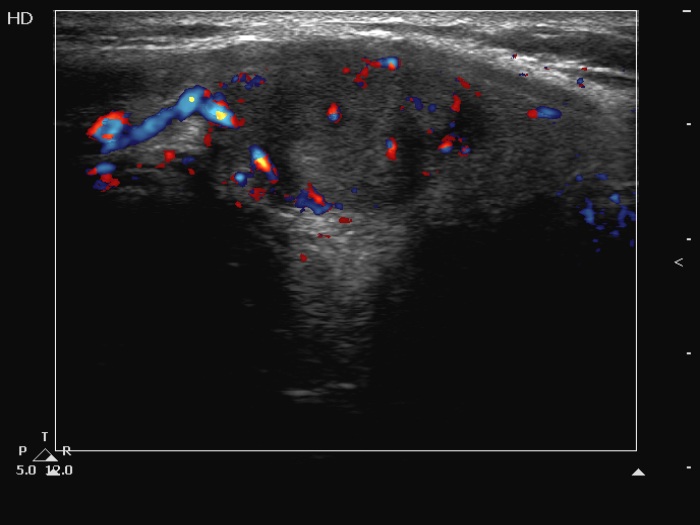

Right lobe, longitudinal scan

Left lobe, longitudinal scan. The nodule shows intranodular vascularity.